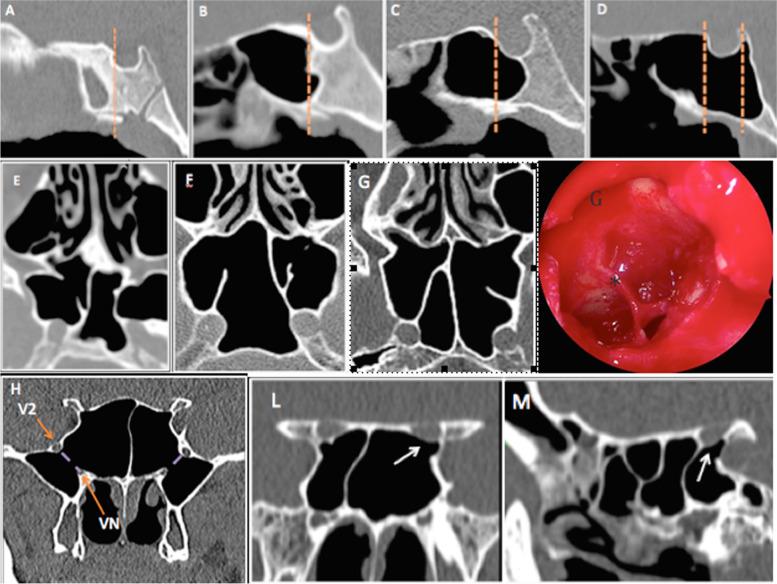

Risky anatomical variations of sphenoid sinus and surrounding structures in endoscopic sinus surgery.

This study aimed to examine the relationship between the sphenoid sinus (SS) and surrounding vital structures such as the internal carotid artery (ICA) and optic nerve canal (ONC) as well as the types of attachment of the sphenoidal septa onto these structures.

In total, 230 computed tomography (CT) scans were reviewed to study the type of sphenoid sinus pneumatization (SSP), the protrusion and dehiscence of the ICA and ONC, the relationship between the sphenoidal septa and surrounding vital structures as well as pterygoid recess pneumatization (PRP).

The most common SSP was sellar type (58.7%). The rates of protrusion and dehiscence of the ICA were 26.3 and 0.4%, and for the ONC, they were 13 and 1.5%, respectively. The ICA and ONC were most protruded and dehiscent in more extensive SSP. In 21.6% of patients, the intersphenoidal septa (IS) were attached to the wall of the ICA and in 8.6% they were attached to the wall of the ONC. The attachment of IS to the ICA correlated statistically significantly (p < 0.0001) with protrusion of the ICA. Accessory septa were detected in 30.4% of cases with various sites of attachment.

To reduce the risk of injury and complications during endoscopic sinus surgery (ESS), surgeons should consider using CT to identify possible bulging and dehiscence of the ICA/ONC and their relationship to the extent of SSP and also to establish the presence of deviation of the sphenoid septum, and the presence of accessory septa.